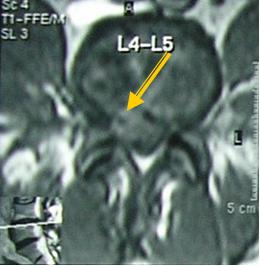

Единственно информативным методом в диагностике грыжи МПД на поясничном уровне является магнитно-резонансная томография (МРТ). Спиральная компьютерная томография (СКТ) имеет гораздо меньшую информативность в диагностике грыж МПД. !!! Хирургическая тактика в лечении межпозвоночных грыж планируется только на основании данных МРТ.